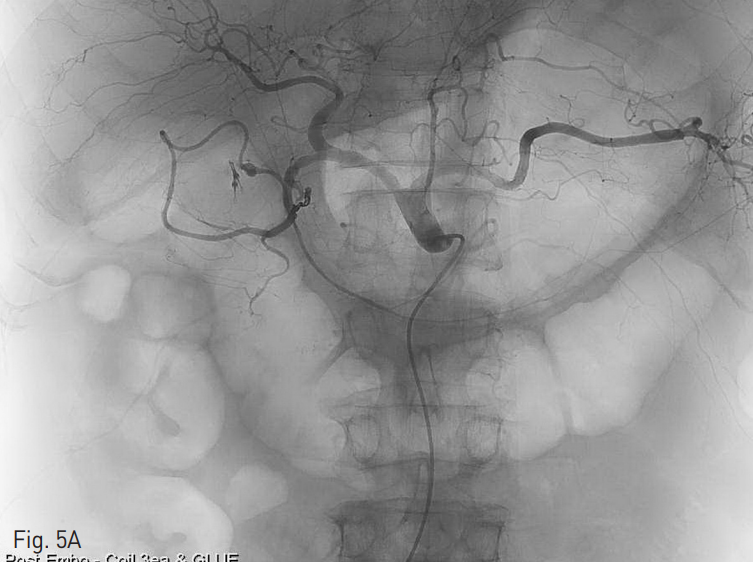

색전술 시행 후 복강동맥 (Fig. 5A), 위창자간막동맥 혈관조영술 (Fig. 5B) 모두에서 잔류 혈관외유출은 보이지 않았다.

Fig. 5

(A) Celiac and (B) Superior mesenteric arteriography shows no apparent extravasation.